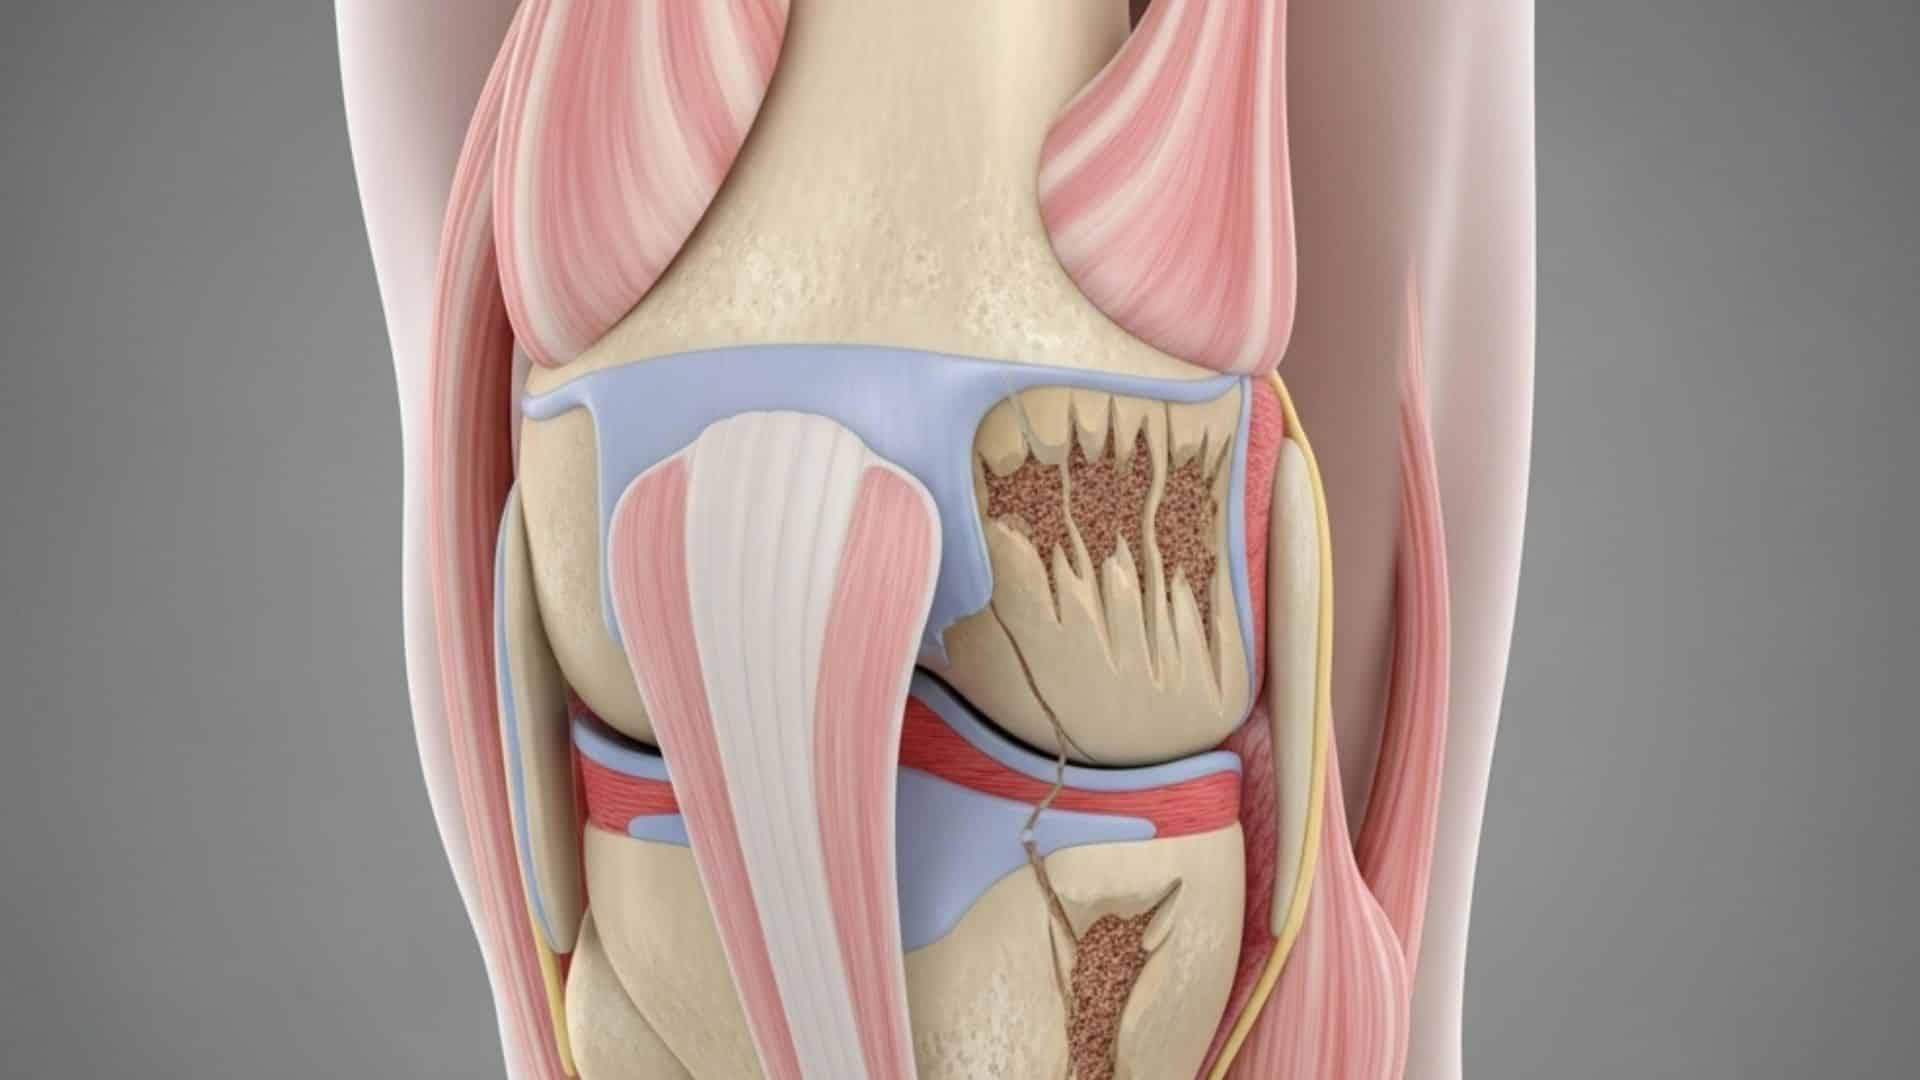

2. Arthritis (osteoarthritis)

Joint pain and stiffness develop when protective cartilage wears down over time. About 17% of adults over 50 experience foot arthritis. Symptoms include reduced flexibility, swelling, and grinding sensations in joints.

Weather changes can make arthritis pain worse, and morning stiffness is common. The condition often affects multiple joints in the foot simultaneously.

20. Bone Spurs

Bony projections form along bone edges, often due to arthritis. Nearly 60-80% of people over 50 develop bone spurs. They cause sharp, stabbing foot pain and difficulty walking.

Bone spurs can form anywhere in the foot but commonly affect the heel and toe joints. They may not cause pain until they rub against other bones or soft tissues.